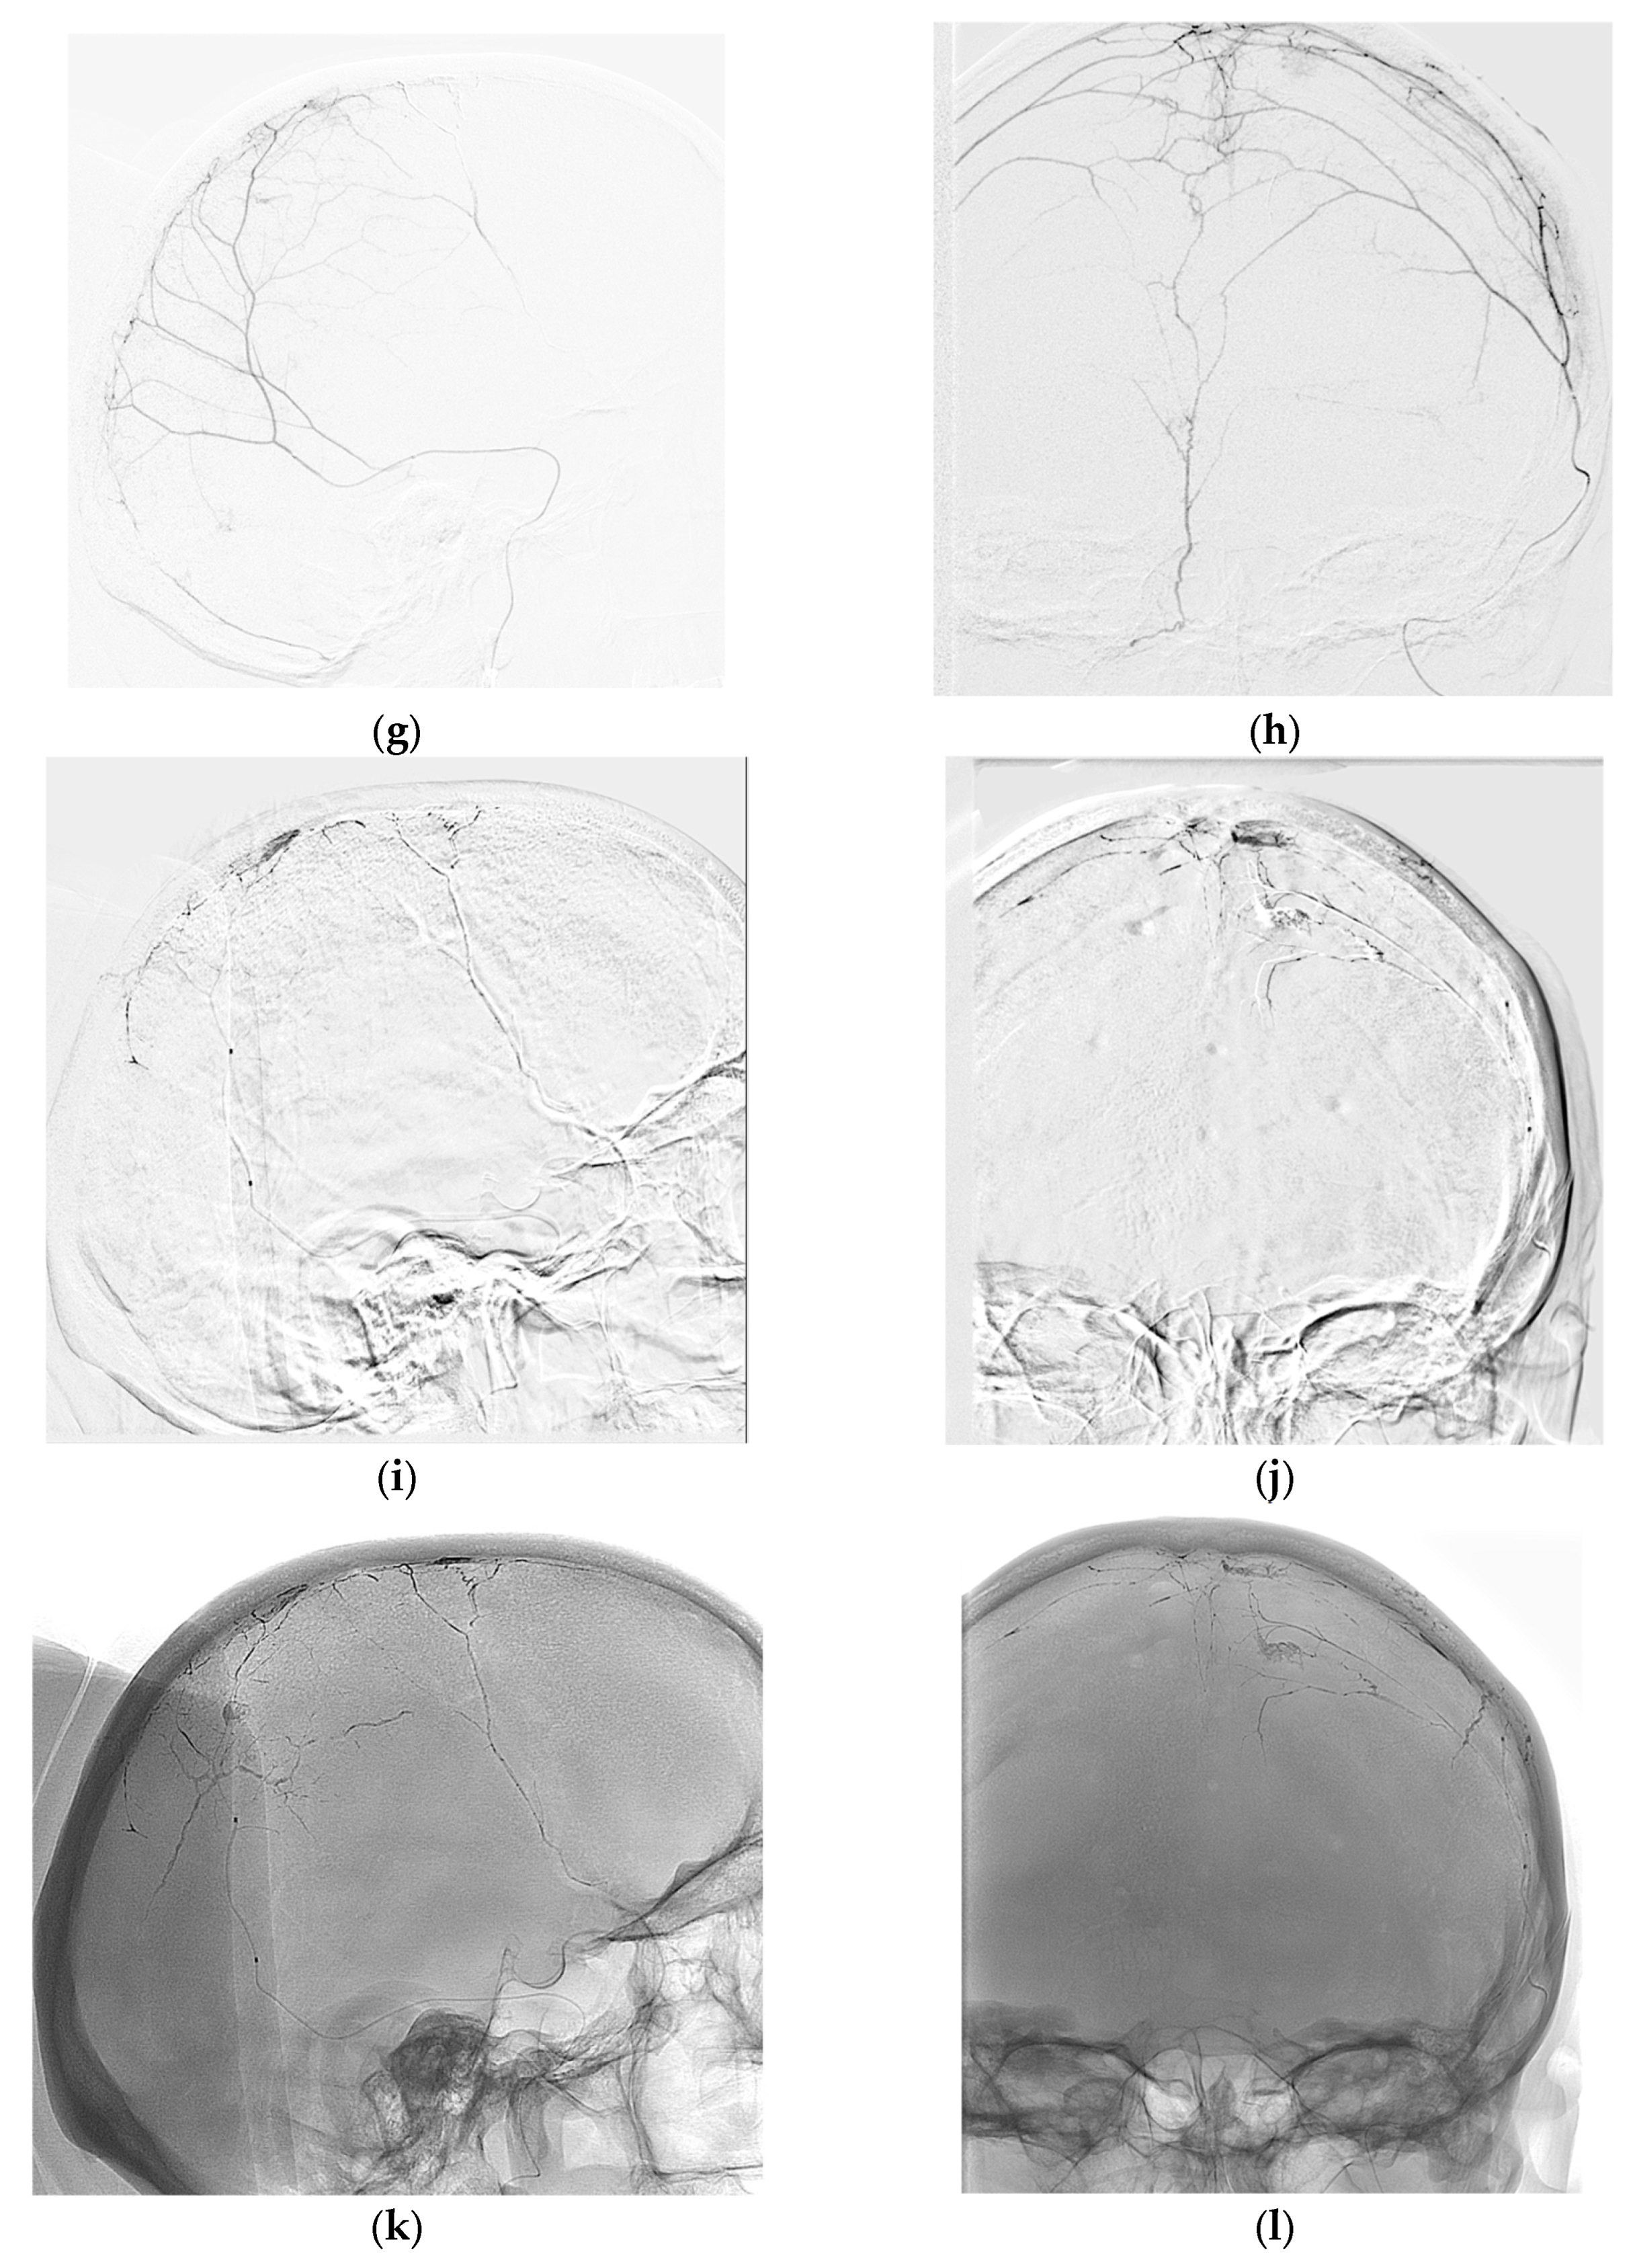

During the brain MRI in May 2022, a small parasagittal meningioma (12.9 x 11 mm) was detected in the left frontal region without brain compression or perifocal edema, and it was not invading the upper sagittal sinus. Figure 1a,b provide a visual representation of this finding.

Considering the size of the lesion and the absence of any perifocal complications, radiosurgical treatment was recommended using the Lexell Gamma Knife. However, the patient declined radiation therapy. A repeat MRI scan of the brain conducted in May 2023 (Figure 1 c and d) showed an increase in the size of the lesion by 2 millimeters (14*11*12 mm). The patient continued to decline radiation therapy, and therefore, the medical expert panel recommended proceeding with the first stage of embolization of the middle meningeal artery (MMA) and its branches with a follow-up. And to perform surgical removal of the tumor if it would be necessary.

Figure 1. Magnetic resonance imaging (MRI) of the brain revealed an increase in the size of a parasagittal meningioma (white arrows) in the left frontal region over the course of one year prior to embolization: (a) A T1-weighted image taken in the sagittal plane and (b) a T2-weighted image acquired in the coronal plane demonstrates the meningioma before embolization, with dimensions of approximately 12 ×9 ×11 millimeters; (c) A T1-weighted scan in the sagittal view and (d) a T2-weighted image acquired in the coronal plane shows the meningioma at approximately one week before embolization with dimensions of 14 ×11 ×12 millimeters.